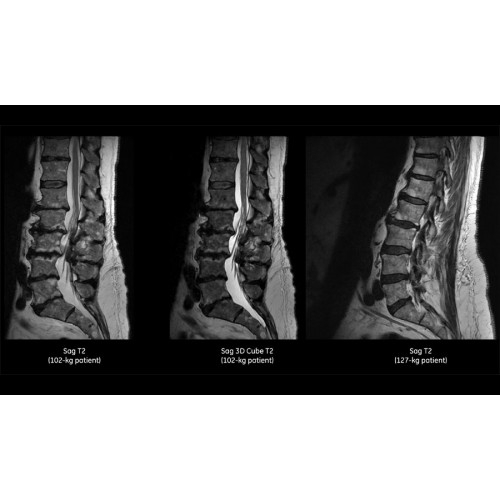

- Технология Digital Surround Technology (DST) — это новая технология объемной оцифровки данных, объединяющая сигналы от каждого элемента катушки. Прекрасное соотношение сигнал/шум и чувствительность поверхностных катушек в сочетании с превосходной однородностью и высокой проникающей способностью встроенной радиочастотной катушки — все это позволяет создавать качественные изображения не только позвоночника, но и всего тела.

Помимо технологии 97 РЧ-каналов, SIGNA Pioneer использует магнит 3.0Т высокой однородности, предназначенный для повышения качества визуализации во всех областях, а также закладывающий прочный фундамент для долгосрочных инвестиций и роста клинических возможностей.